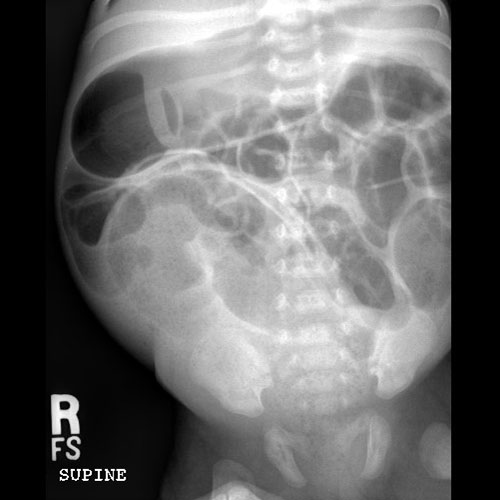

KUB/Supine Abdomen.

Scout Image of the abdomen

There is dilatation with gas or fluid of multiple or diffuse loops of bowel.

​Both the small and large bowel are filled with air and/or fluid and may or may not be distended.

There is a large amount of stool burden.